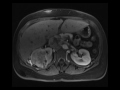

Renal Cell Carcinoma (RCC) with vascular invasion